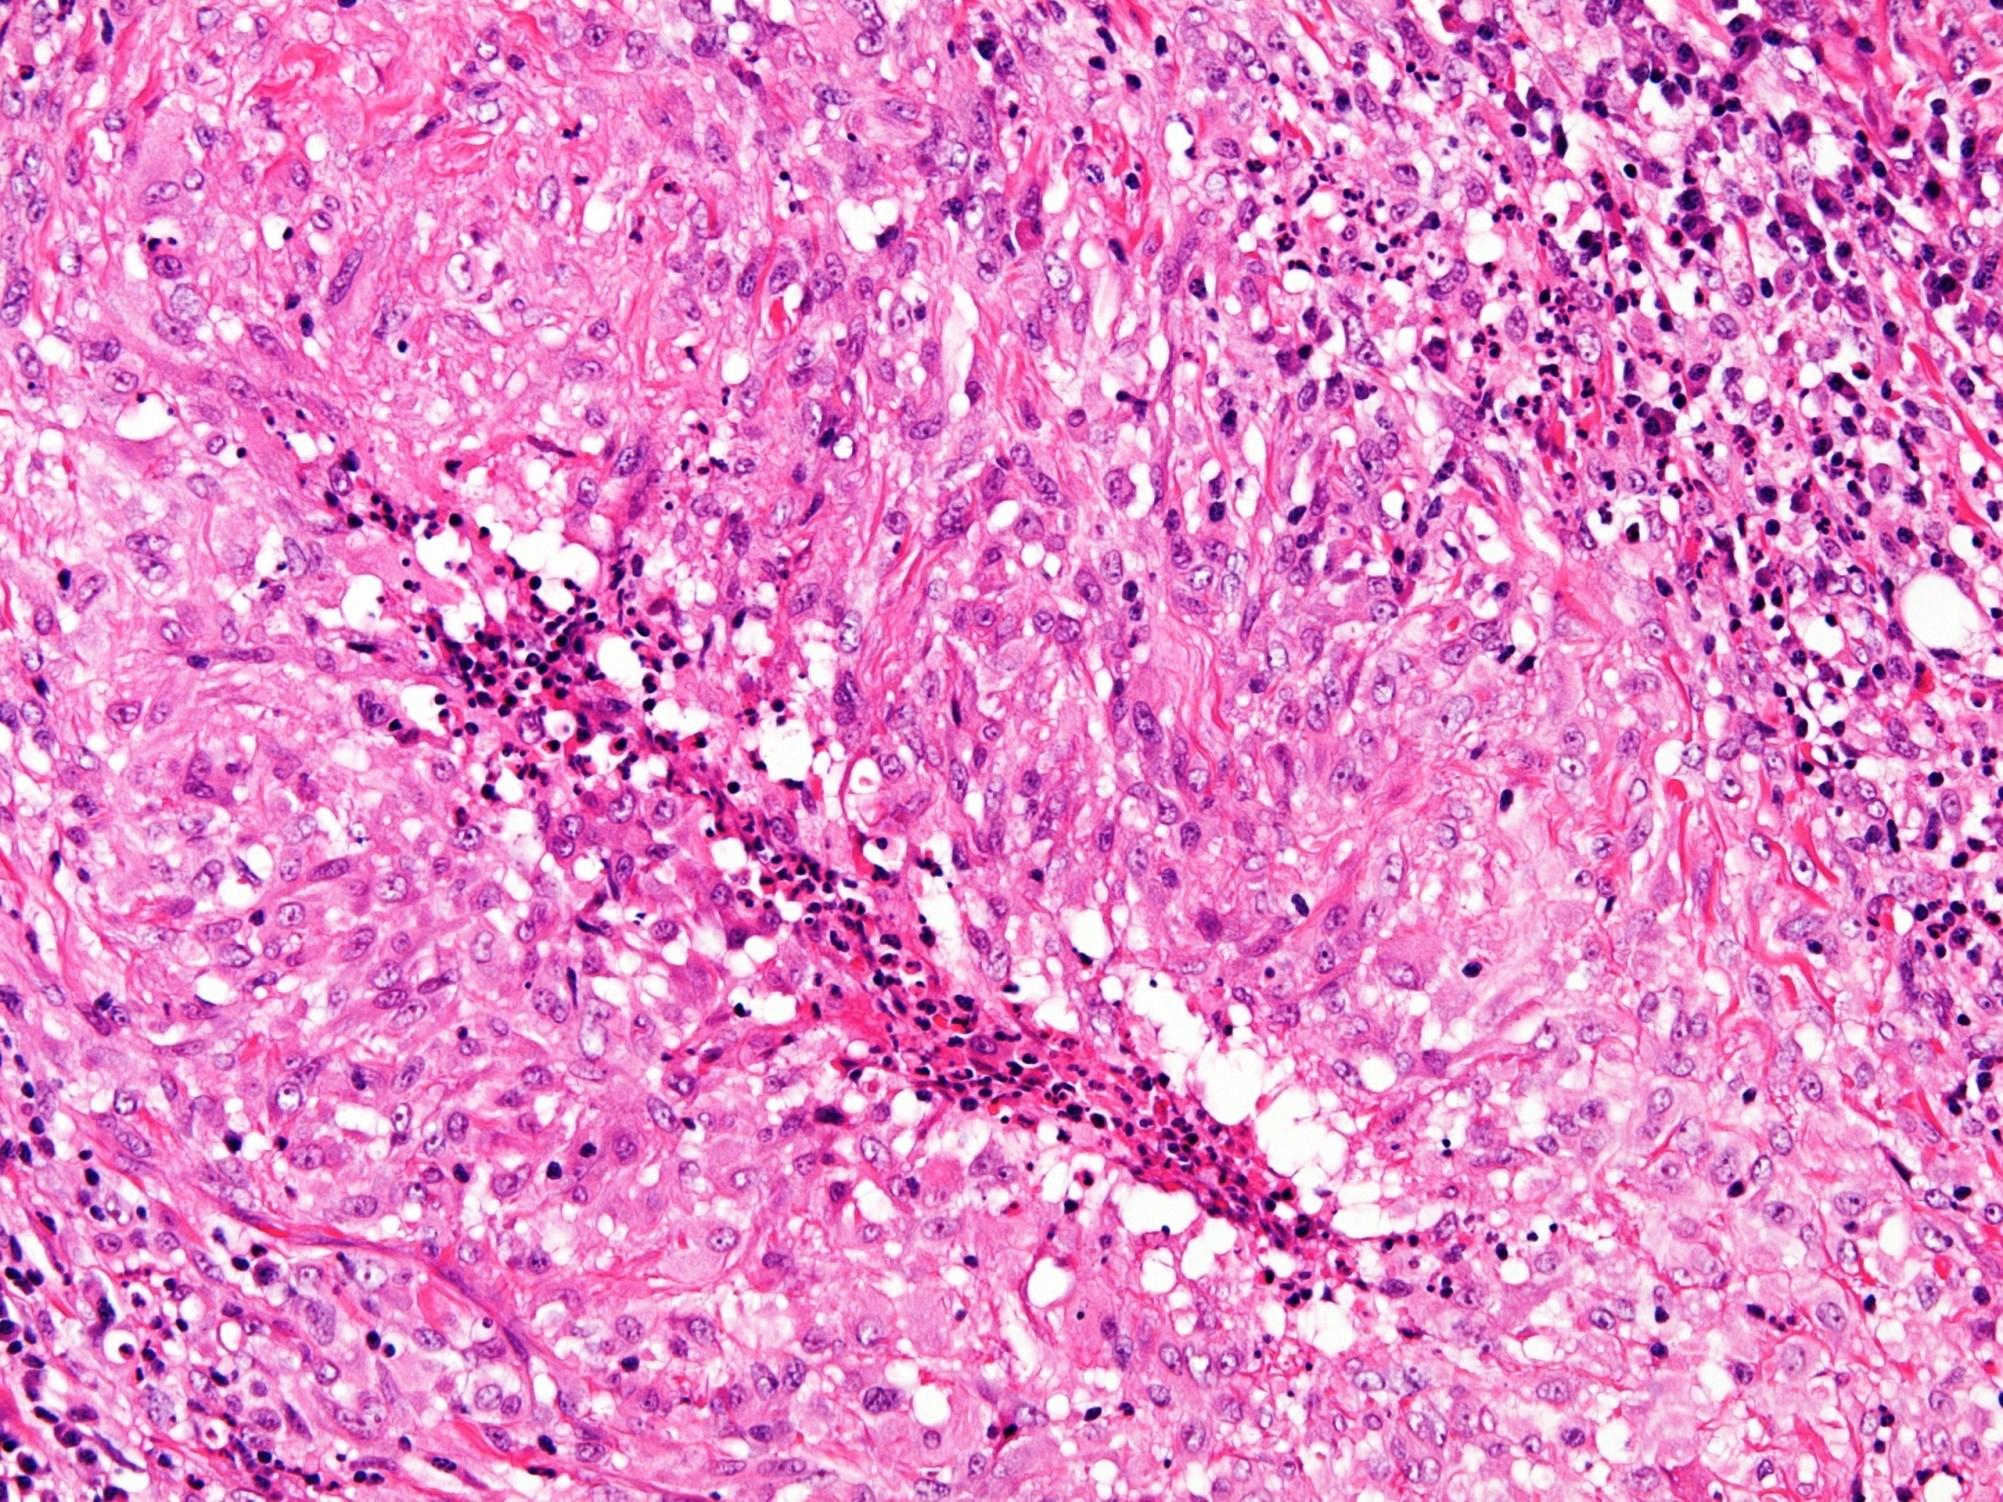

Pleomorphic adenoma

 Pleomorphic refers to variety of cells and architectural patterns not to cytomorphology

 The most common benign tumour

 Tumours of minor glands can be non or poorly encapsulated

 Ductal / luminal cells and abluminal myoepithelial population

 Myoepithelial population often most prominent

Myoepithelial cells

Hyaline plasmacytoid

Clear

Spindled

Epithelioid

Stroma

Myxoid

Chondroid

Hyalinised

Fibrous

(Bone)

Bosselated multinodular growth

Malignant transformation